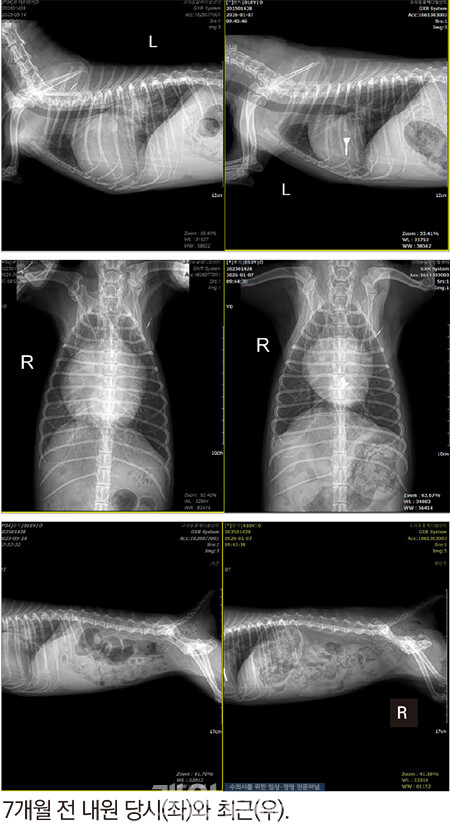

이 아이가 최근에 재진을 왔다. 심장만 쳐다보고 있다가 오랜만에 복부 방사선을 좀 비교해 봤는데!!

오…. 간이 작아졌다 !!!!!!!!!!!!!!!!!!!!!

심장은 내가 예상하고 바랬던 수준보다 더 멋지게 작아졌다. 봉지가 해냈다.

봉지는 우심에서 폐로 피를 못 보내서 간 울혈이 있었고, 그래서 간이 컸는데, 지금은 간이 작아진 걸로 보아 우심이 폐로 피를 잘 보낸다는 이야기이다. 순환이 아주 잘 된다는 이야기이다.

봉지는 잘 지낸다. 살이 통통하게 400g 이나 쪘다. 심장이 좋아지고 순환이 좋아지면 다른 장기가 좋아진다. 신비로운 순환의 세계이다. 그러니까 심장이 작아진 것+간이 작아진 것은 엄청난 의미가 있는 것이다.